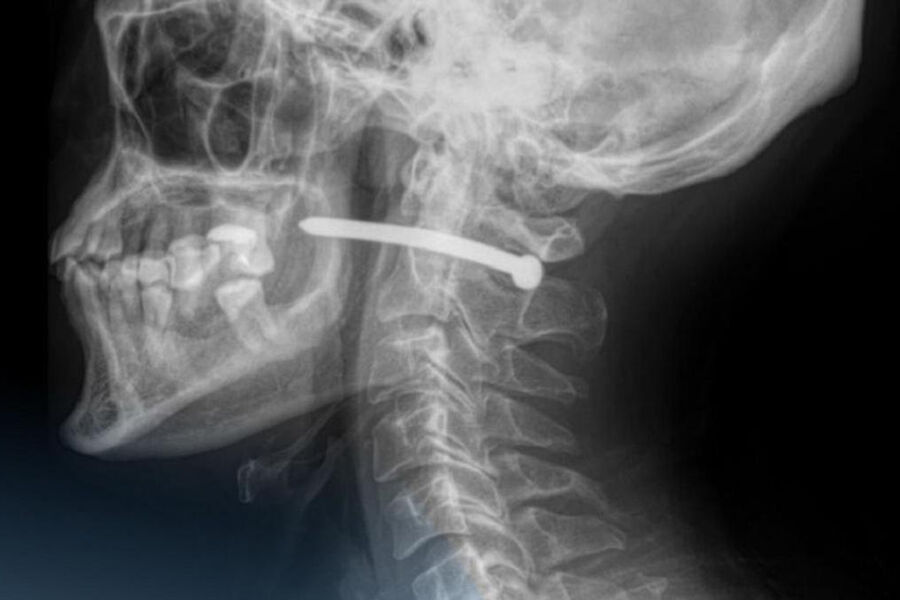

В Петропавловске 51-летний мужчина обратился в городскую больницу скорой помощи с ранением за ухом. Как выяснилось, во время ремонта он случайно получил травму — в него выстрелил гвоздь из пневматического пистолета.

Рентген показал, что металлический предмет прошел буквально в миллиметрах от шейного отдела позвоночника. Медики отметили, что мужчине невероятно повезло — жизненно важные органы и сосуды не были повреждены.